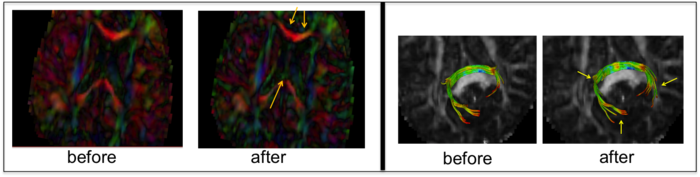

The correction results show visible improvement in contrast within the cingulum and fornix tracts (left) and fiber tractography of splenium (right).